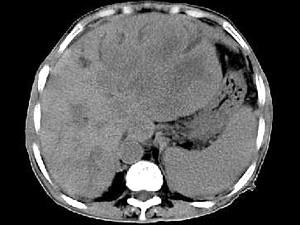

问题 女,73岁,中上腹痛一月余,患者黄疸、消瘦,CT检查如下图,最可能的诊断是 ( )

选项 A、肝淋巴管瘤 B、肝胆管细胞癌 C、巨块型肝癌 D、肝血管瘤 E、肝脓肿

答案 C